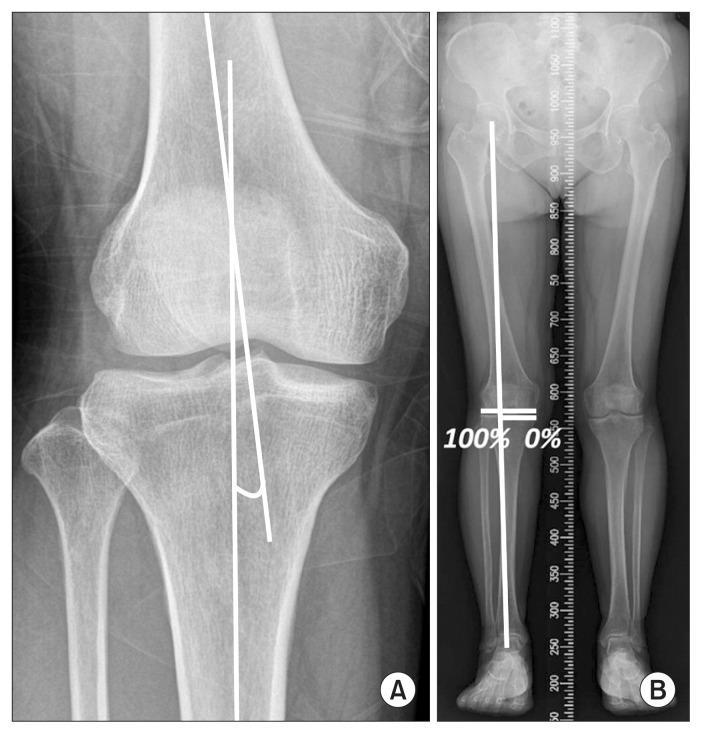

Forty-five patients were divided into the HTO (n=23) and UKA (n=22) groups. Clinically, we evaluated the Lysholm knee scoring scale, visual analogue scale, Hospital for Special Surgery, and Western Ontario and McMaster Universities Osteoarthritis index scores preoperatively, 6 and 12 months postoperatively, and at the final follow-up. Radiographically, we measured the femoral-tibial angle and mechanical axis deviation preoperatively and at the final follow-up.

45例患者被分为HTO组(n = 23)和UKA组(n = 22)。在临床上,我们在术前、术后6个月、12个月以及末次随访时评估了Lysholm膝关节评分量表、视觉模拟量表、特种外科医院评分以及西安大略和麦克马斯特大学骨关节炎指数评分。在影像学方面,我们在术前和末次随访时测量了股胫角和机械轴偏移。